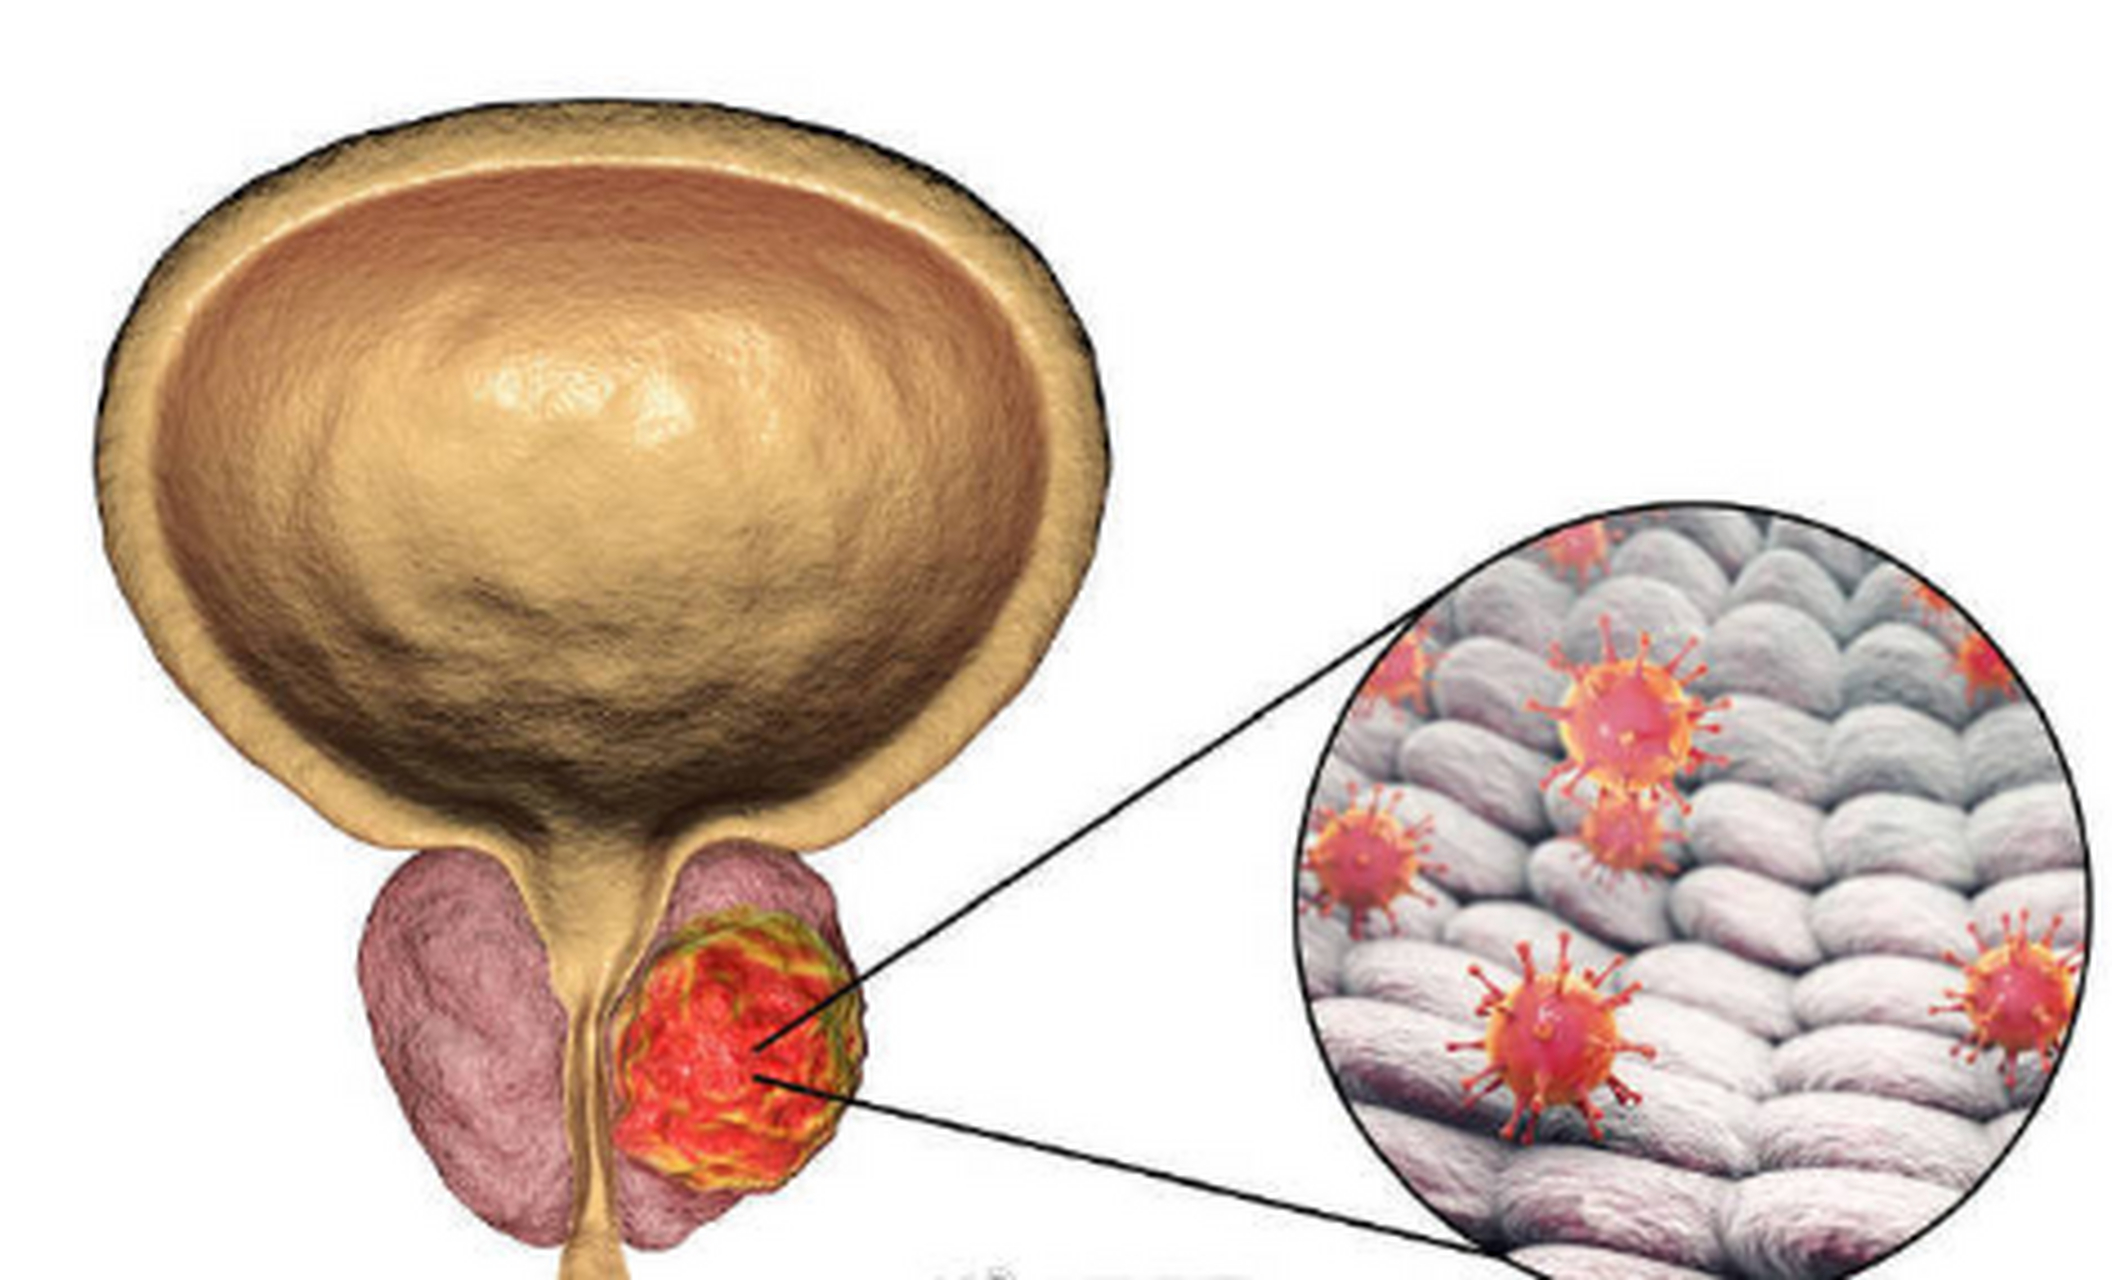

光邦光子治疗仪:前列腺钙化是怎么回事?会不会变成癌?